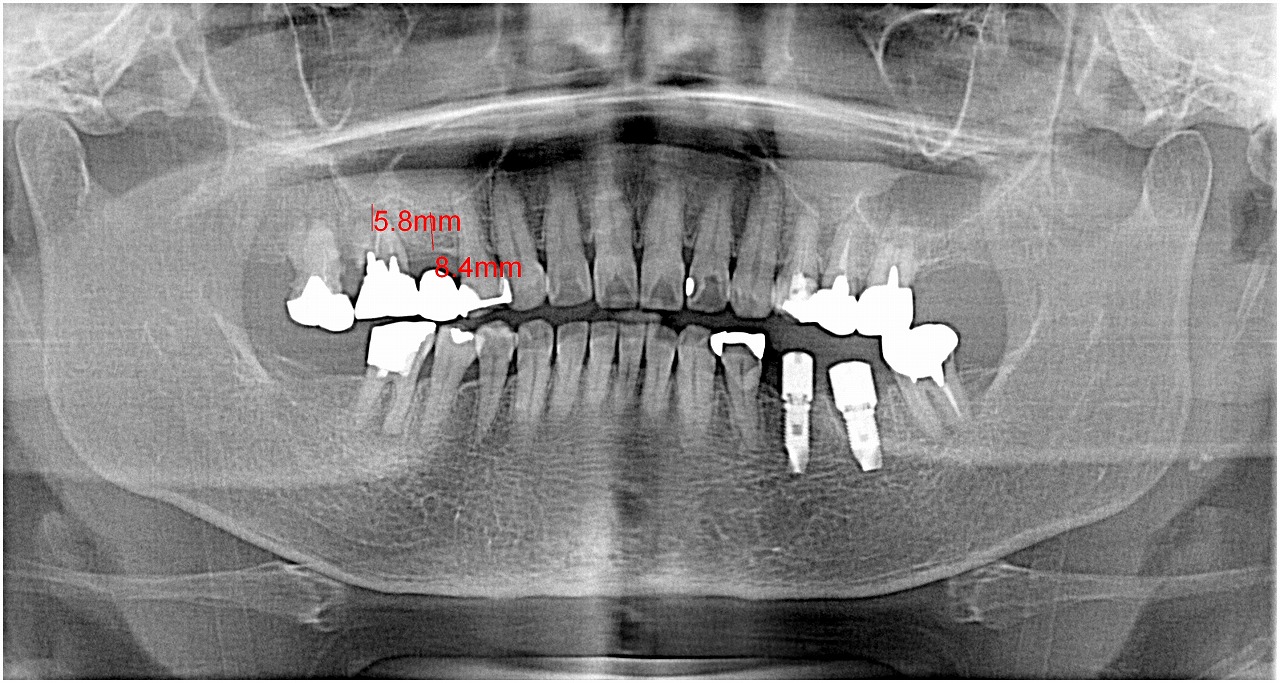

術前のパノラマになります

6番部の支台歯を見ていきます

中は土台も入っていません

歯に穴が開いていて分岐部の骨吸収も生じていました

術後のパノラマになります

綺麗にインプラントが入りました